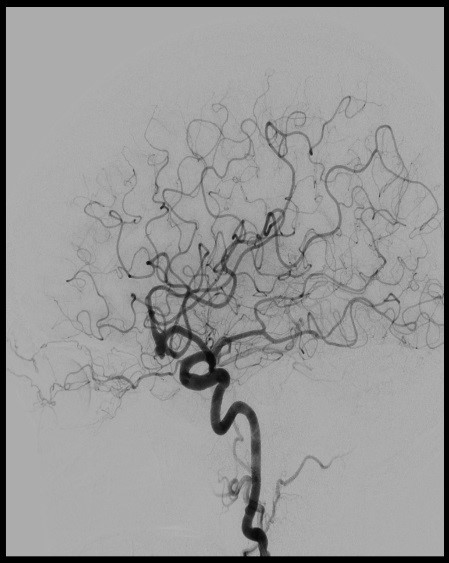

Stroke Imaging Comparison

New Biplane imaging

New Imaging

The biplane utilizes two rotating cameras, one on each side of the patient, to produce simultaneous and highly detailed images of blood vessels, soft tissue, and blood flow in real-time.

3-D biplane imaging helps clinicians path blood flow through vessels, locate blockages that cause ischemic strokes, and identify aneurysms and arteriovenous malformations (a tangle of arteries and veins) that cause hemorrhagic strokes.